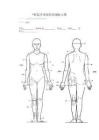

SRSS 的症状通常在手术后数周或数月内出现。这些症状可能包括:手术部位持续性疼痛或不适手术部位压痛或触痛手术部位皮肤的增厚或硬化手术部位的肿胀手术部位的异常感觉,如灼烧感或刺痛感